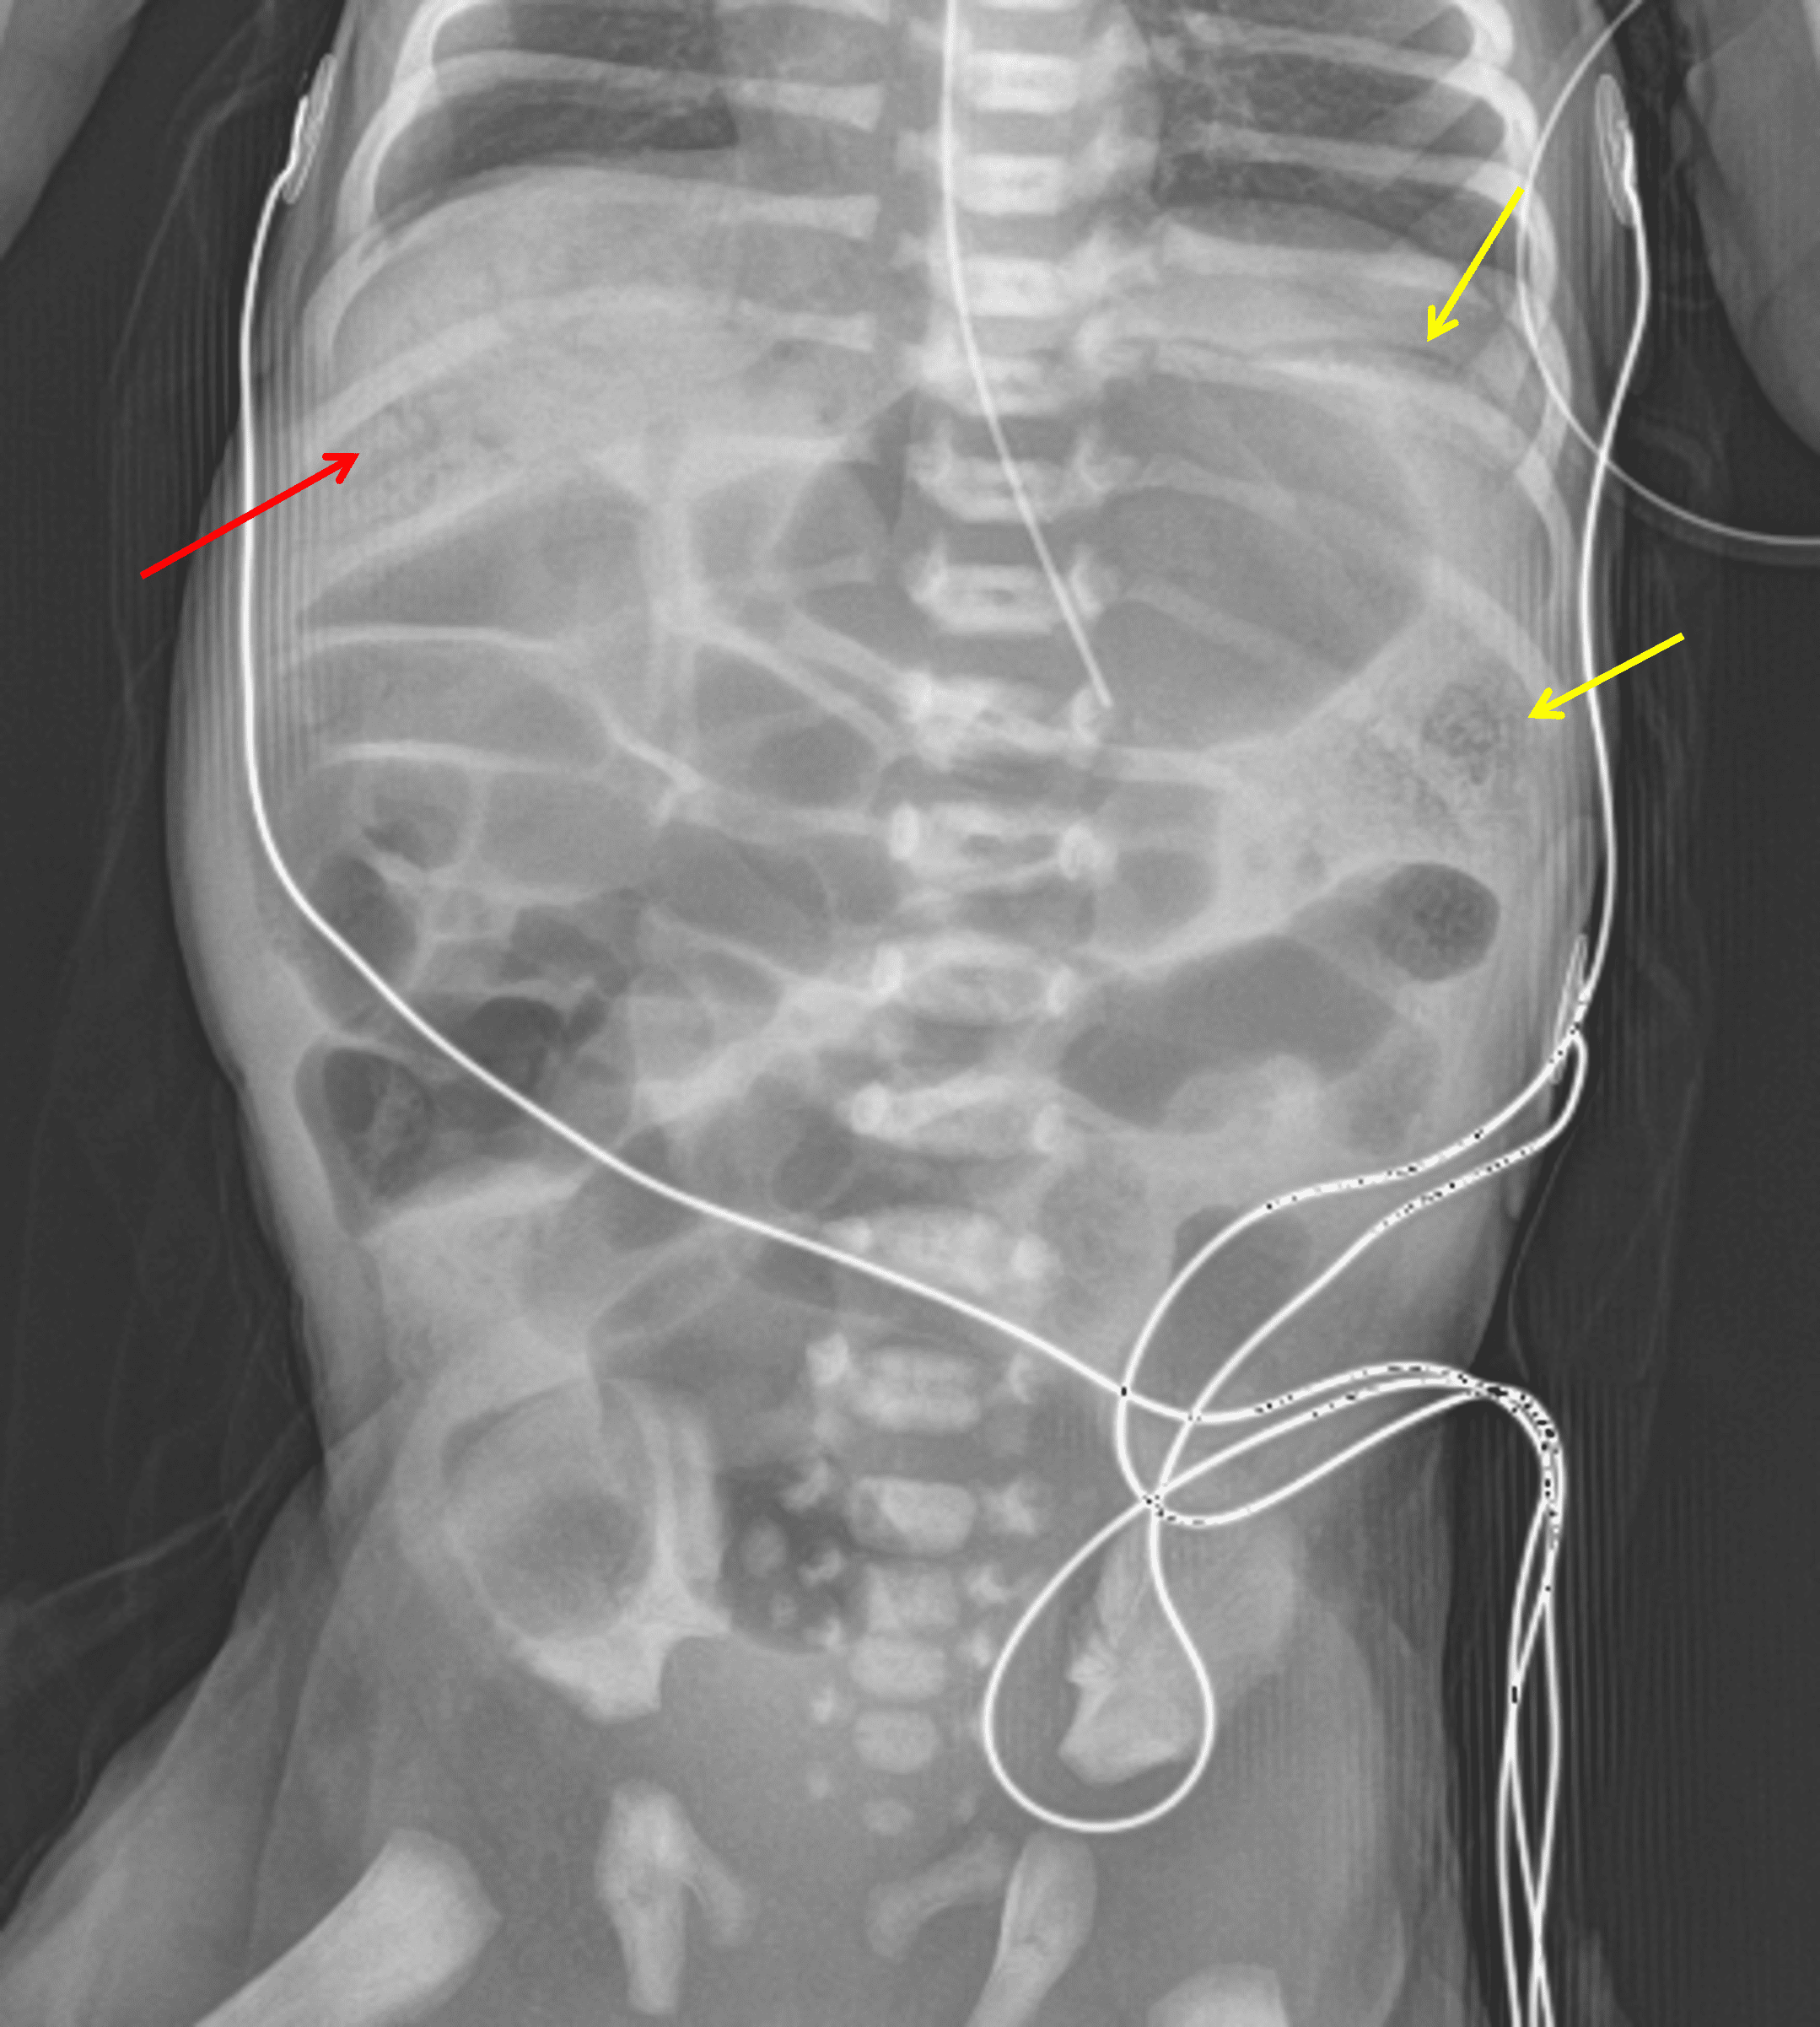

Demographics: 7 days old, Female

Indication: Melena (term delivery)

• Extensive portal venous gas

• Mottled and curvilinear lucencies along loops of bowel in the left upper quadrant

• No definite evidence of pneumoperitoneum

• Nonfocal gaseous distension of bowel loops throughout the abdomen

• Enteric tube tip overlies the stomach

Necrotizing enterocolitis (NEC)

Findings concerning for necrotizing enterocolitis with extensive portal venous gas as well as mottled and curvilinear lucencies along loops of bowel in the left upper quadrant suspicious for pneumatosis.

No definite evidence of pneumoperitoneum. However, recommend left side down decubitus view for a more sensitive evaluation.

Nonfocal gaseous distension of bowel loops throughout the abdomen.

Enteric tube tip overlies the stomach.

Red arrow: multiple branching lucencies overlying the liver consistent with portal venous gas. Yellow arrows: curvilinear and mottled lucencies along bowel loops in the left upper quadrant.